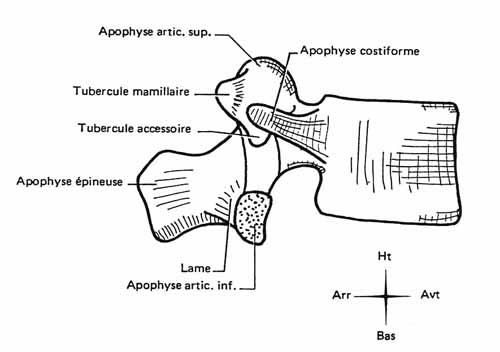

Tu peux analyser les lames sur le cliché de profil pour le rachis cervical, dorsal et lombaire ainsi que sur l’incidence de ¾ de lombaire où tu déroules les chiens de la chapelle

Les pédicules tu les analyses en coupe optique sur les incidences de face et sur le profil

Rachis cervical:  Rachis dorsal: Rachis dorsal:  Rachis lombaire: Rachis lombaire:   1. Processus articulaire supérieur 2. Pédicule droit 3. Processus transverse droit 4. Isthme 5. Processus articulaire inférieur 6. Lame opposée 7. Processus transverse opposé 8. Epineuse 9. Interligne articulaire postérieure 10. Processus articulaire inférieur opposé 11. Processus articulaire supérieur opposé Pour ce qui est de la radioanatomie; nous te laissons le soin d'apprendre tout cela grâce aux livres à ta disposition et à tes stages surtout!  Nous avions commencé une liste de livres de radiologie; à toi de t'en servir et bonnes recherches! Si tu souhaites trouver d'autres correspondances, si quelques détails t'interpellent n'hésite pas à poser des questions précises! Bon courage la marmotte!